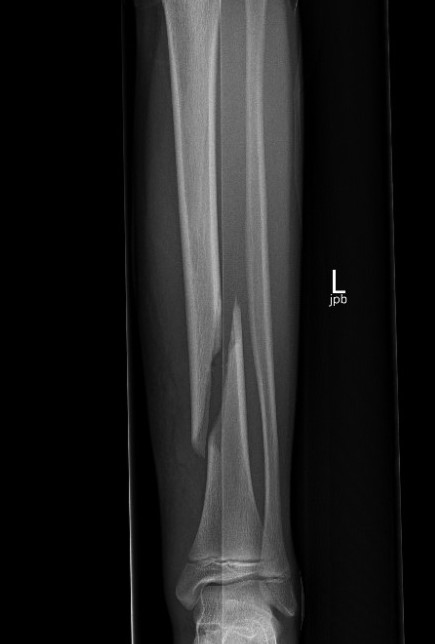

Displaced Tibial Shaft Fractures

Acceptable reduction

- varus / valgus < 5o

- anterior / posterior < 5o

- rotation 5o

- shortening 10 mm